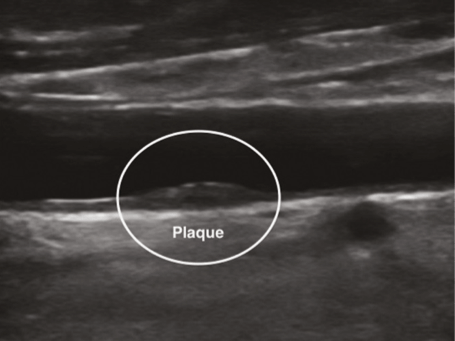

Так выглядит УЗ-картина атеросклеротической бляшки в просвете артерии

1). Сонные (общие, наружные и внутренние) и позвоночные артерии - они кровоснабжают головной мозг и наличие бляшек в этом бассейне создает риск инсульта